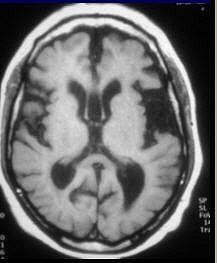

![]() |

| Enlarged sylvian cisterns in NPH. Studies have indicated that the sylvian CSF volume in patients with idiopathic NPH is significantly greater than in patients with Alzheimer's disease (AJNR, August 1998, Vol. 19:7, pp. 1277-1284). Image courtesy of Dr. William Bradley Jr., Ph.D. |